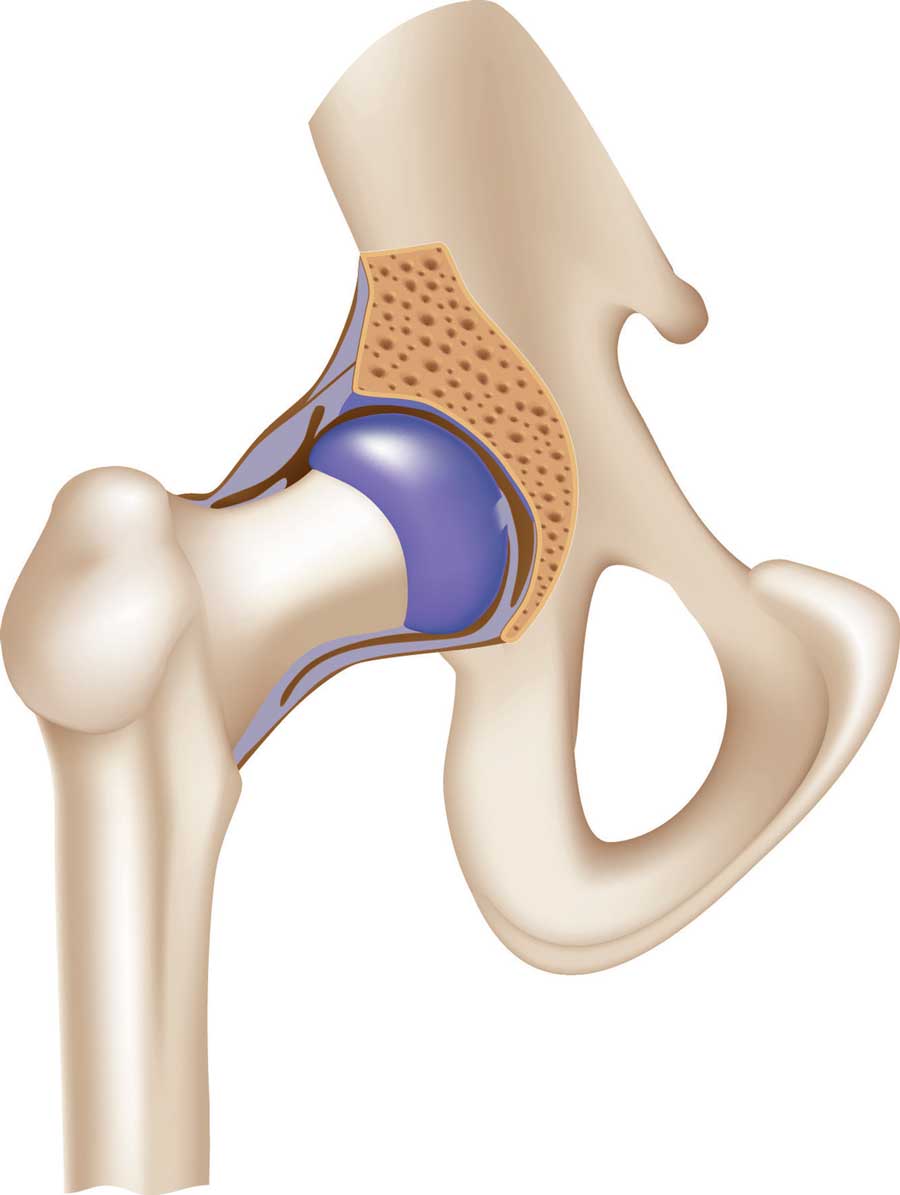

Сустав – самая распространенная и сложная форма соединения костей. Обязательными элементами любого сустава, независимо от места расположения и степени подвижности, являются суставные поверхности, суставная сумка и суставная полость.

Соединение костей в коленном суставе (вверху – рентген, внизу – модель)

Суставные поверхности костей, образующие сустав, плотно прилегают друг к другу. Они покрыты особым гиалиновым хрящом, чья гладкая поверхность и эластичность облегчают движение в суставе, смягчают испытываемые им толчки и сотрясения.

Суставные поверхности костей окружает суставная капсула – оболочка из соединительной ткани. Обычно она крепится к костям в месте перехода суставной поверхности в надкостницу и прочно с ней срастается. Снаружи капсула укреплена связками, которые располагаются в местах наибольшей нагрузки.

Суставные поверхности и капсула ограничивают собой небольшое герметично закрытое пространство – полость сустава, заполненную малым количеством вязкой синовиальной жидкости, роль которой заключается в уменьшении трения в суставах при движении. Благодаря отрицательному давлению в суставной полости поверхности костей тесно прилегают друг к другу.

Суставная капсула

Шаровидный сустав

По форме суставных поверхностей различают плоские, цилиндрические, эллиптические и шаровидные суставы. Наименее подвижны плоские суставы, наиболее – шаровидные.